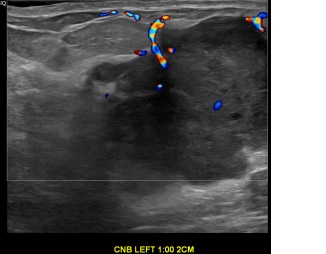

상기환자는 좌측유방 만져지는 멍울로 내원하신 50대중반

여성분으로 의심스러운 좌측혹 조직검사 시행해  침윤성암으로 진단되었습니다